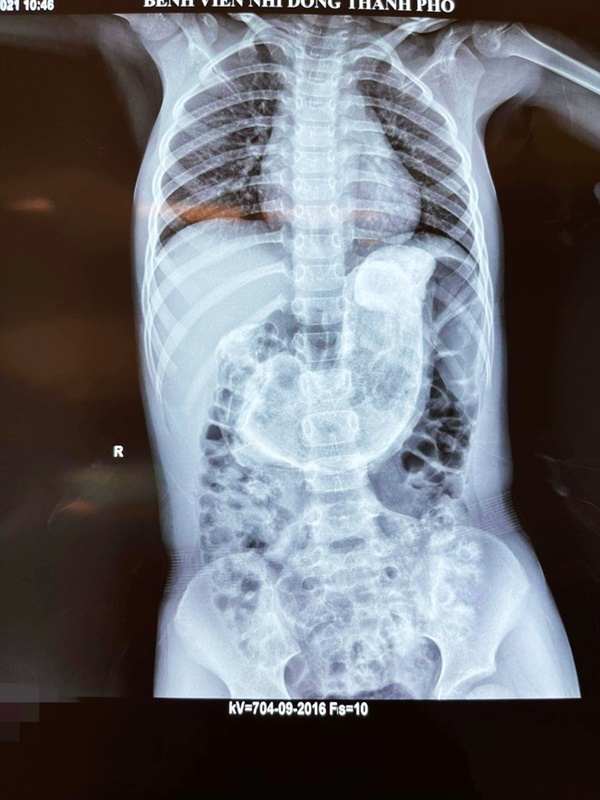

Bệnh viện địa phương sau khi khám, xét nghiệm chụp chiếu nghi ngờ một thể tắc ruột Trichobezoar (thể kết của tóc). Tình trạng hiếm gặp này được đặc trưng bởi sự tắc nghẽn đường ruột do ăn tóc và xảy ra chủ yếu ở những bệnh nhân được chẩn đoán mắc bệnh trichotillomania, một tình trạng tâm lý biểu hiện thôi thúc người bệnh nhổ tóc và ăn không kiểm soát.